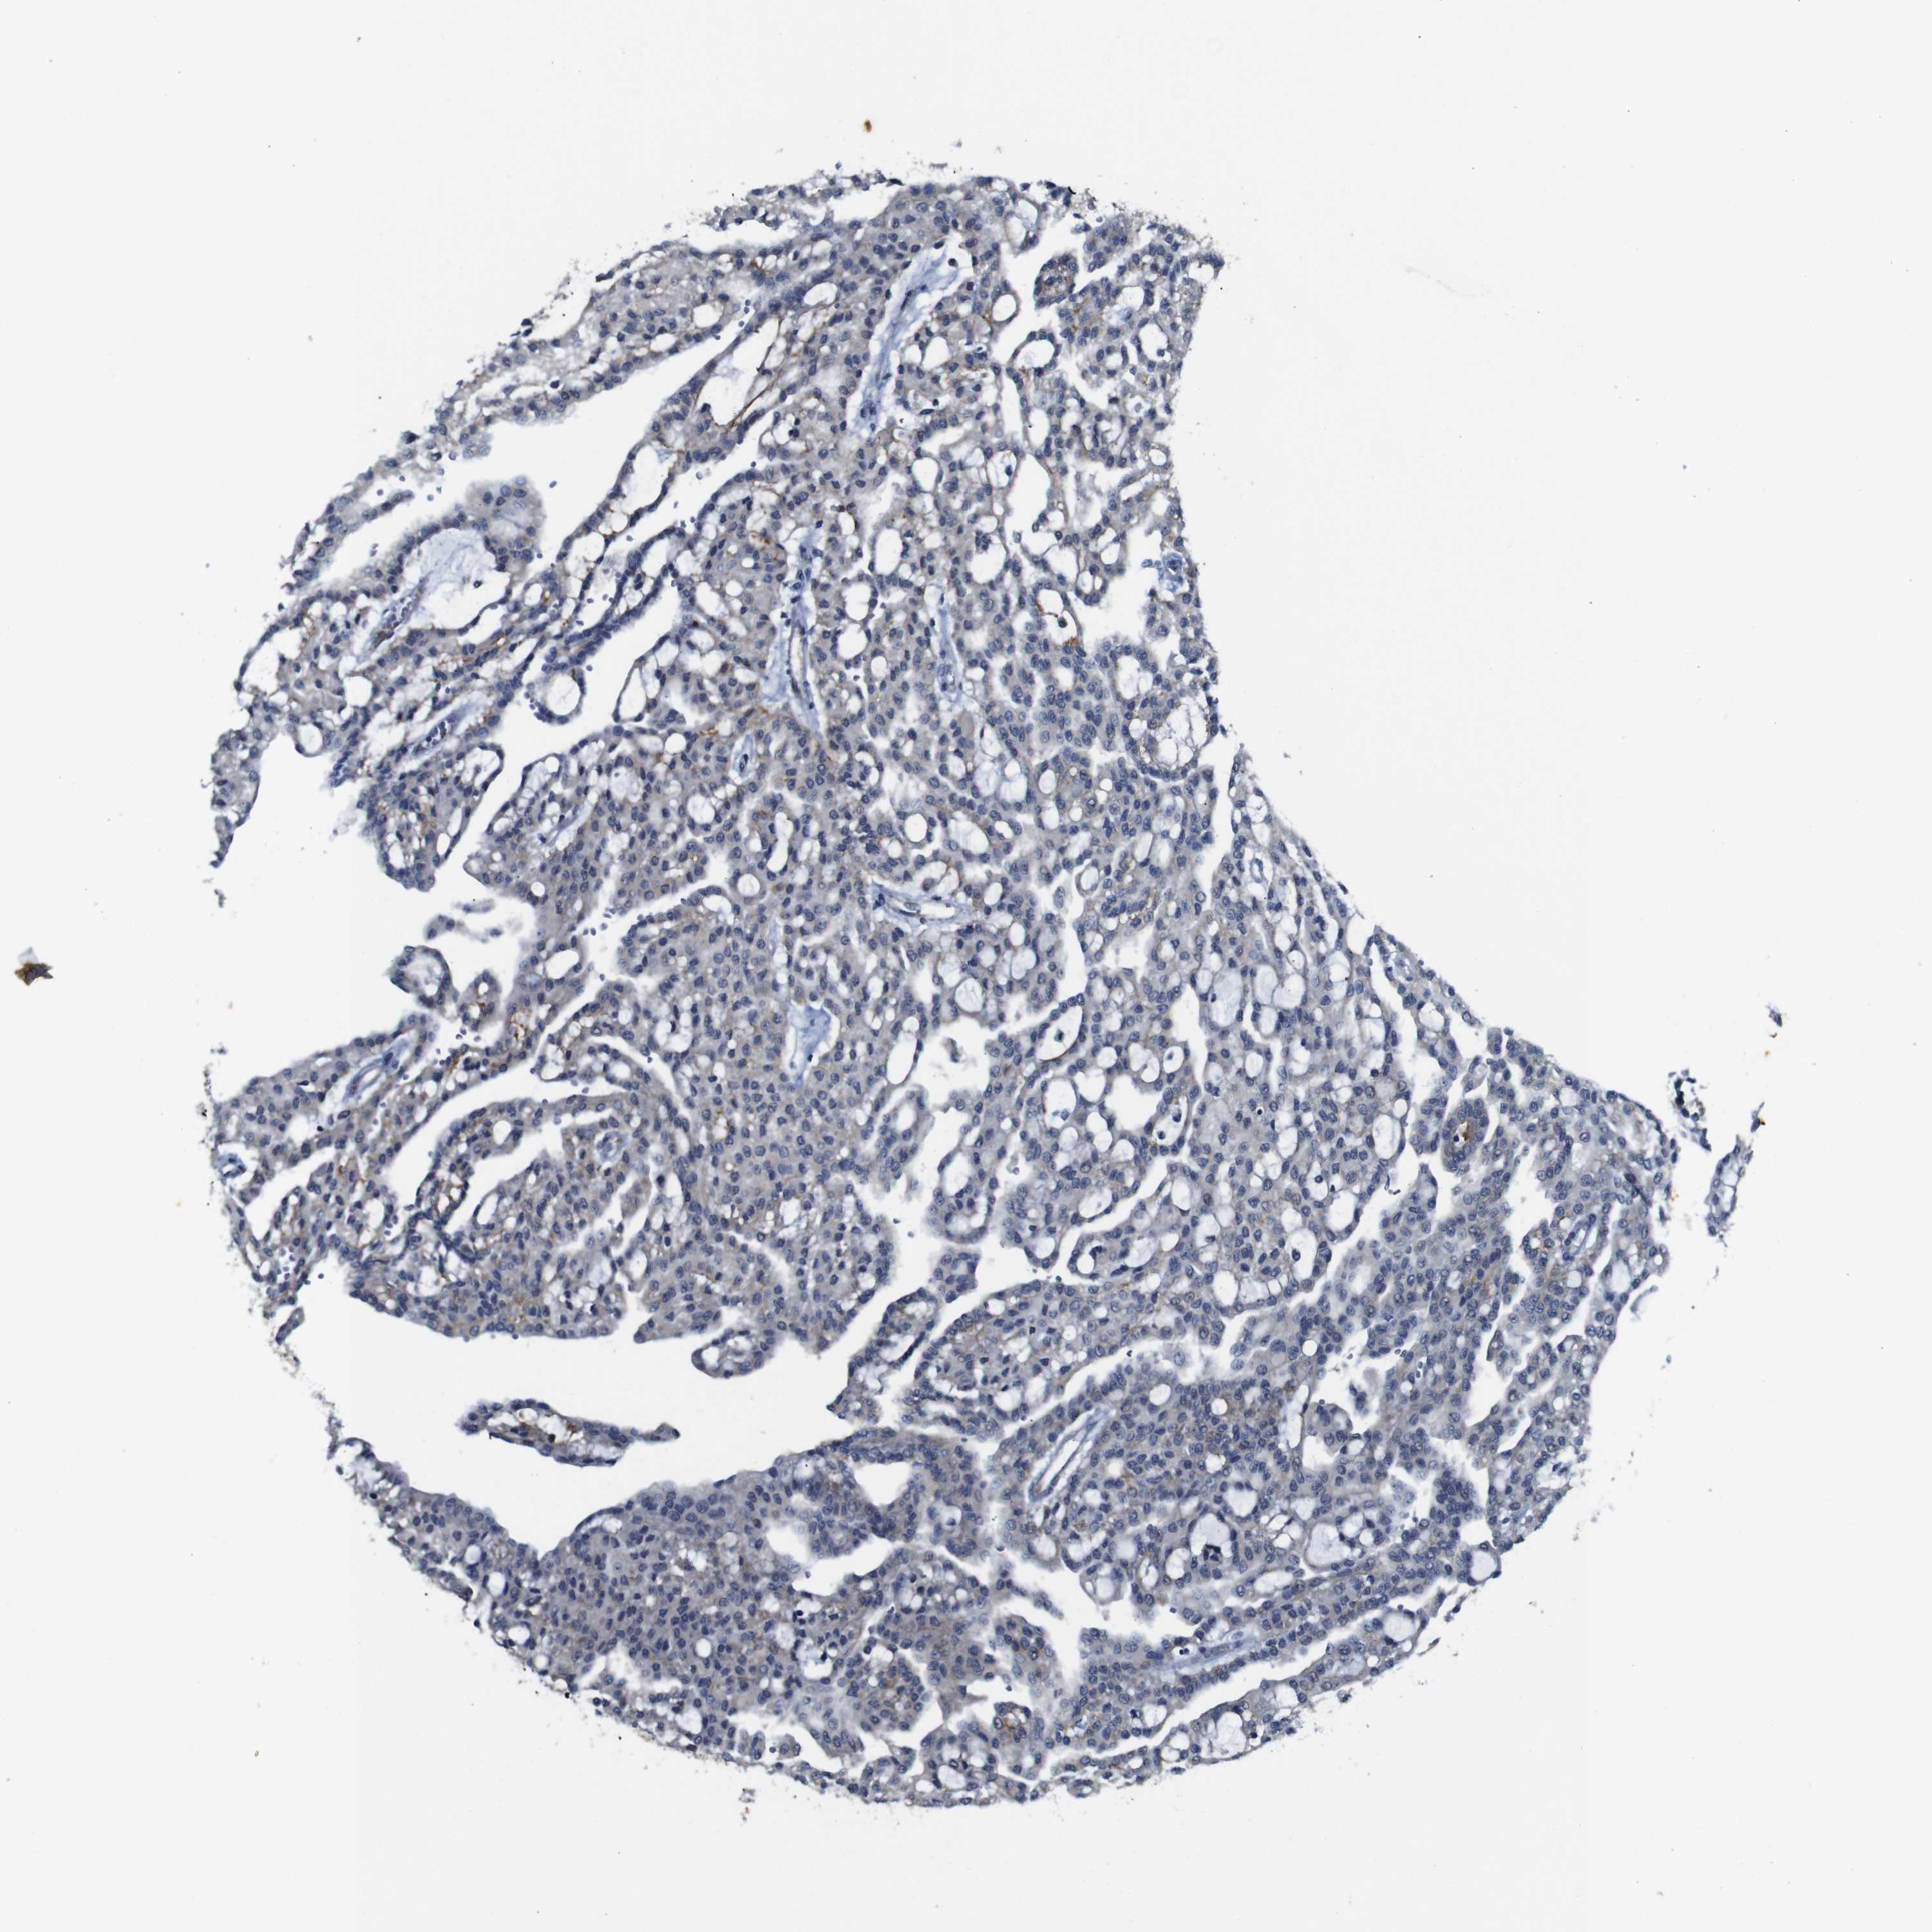

KIDNEY RENAL CLEAR CELL CARCINOMA (VALIDATION) - Interactive survival scatter ploti

The Survival Scatter plot shows the clinical status (i.e. dead or alive) for all individuals in the patient cohort, based on the same data that underlies the corresponding Kaplan-Meier plots. Patients that are alive at last time for follow-up are shown in blue and patients who have died during the study are shown in red.

The x-axis shows the expression levels (FPKM) of the investigated gene in the tumor tissue at the time of diagnosis. The y-axis shows the follow-up time after diagnosis (years). Both axes are complimented with kernel density curves demonstrating the data density over the axes. The top density plot shows the expression levels (FPKM) distribution among dead (red) and alive patients (blue). The right density plot shows the data density of the survived years of dead patients with high and low expression levels respectively, stratified using the cutoff indicated by the vertical dashed line through the Survival Scatter plot. This cutoff is automatically defined based on the FPKM cutoff that minimizes the p-score. The cutoff can be changed by dragging the vertical line or by entering a cutoff value in the square labeled "Current cut-off".

Under the Survival Scatter plot the p-score landscape (black curve; left axis) is shown together with dead median separation (red curve; right axis). Dead median separation is the difference in median mRNA expression between patients who have died with high and low expression, respectively. It is calculated as follows: median FPKM expression of dead patients with high expression - median FPKM expression of dead patients with low expression. This is intended to aid the user in visually exploring custom cutoffs and the associated p-scores and dead median separation.

Individual patient data is displayed and can be filtered by clicking on one or more of the category buttons on the top of the page. Categories describing expression level and patient information include: high, low, alive, dead, female, male and tumor stages. The scale of the x-axis can be toggled between linear and log-scale by clicking on the "x log" button. Mouse-over function shows TCGA ID, patient information and mRNA expression (FPKM) for each patient.

& Survival analysisi

Kaplan-Meier plots summarize results from analysis of correlation between mRNA expression level and patient survival. Patients were divided based on level of expression into one of the two groups "low" (under cut off) or "high" (over cut off). X-axis shows time for survival (years) and y-axis shows the probability of survival, where 1.0 corresponds to 100 percent.

FURIN is not prognostic in Kidney Renal Clear Cell Carcinoma (validation)

Best expression cut offi

Based on the FPKM value of each gene, patients were classified into two groups and association between prognosis (survival) and gene expression (FPKM) was examined. The best expression cut-off refers the FPKM value that yields maximal difference with regard to survival between the two groups at the lowest log-rank P-value. Best expression cut-off was selected based on survival analysis .

When clicking on this number, the vertical dashed line indicating cut-off, the interactive survival plot, and the Kaplan-Meier curve will be adjusted to show results based on the best expression cut-off.

: 45.14

TCGA RNA samplesi

RNA-seq data is reported as average FPKM (number Fragments Per Kilobase of exon per Million reads), generated by the The Cancer Genome Atlas (TCGA) .

Normal distribution across the dataset is visualized with box plots, shown as median and 25th and 75th percentiles. Points are displayed as outliers if they are above or below 1.5 times the interquartile range. FPKM values of the individual samples are presented next to the box plot.

Average pTPM 43.6

Number of samples 100